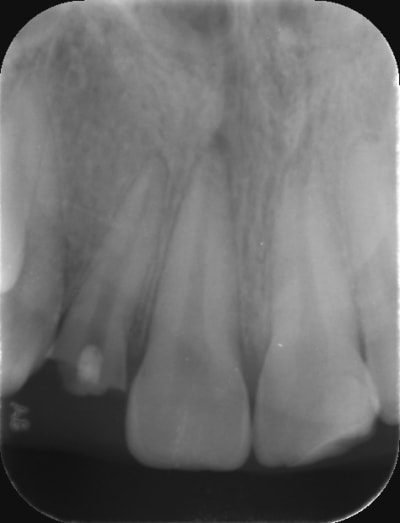

-> et ben voilà un exemple :

- incisive latérale cassée suite à un gros choc vue en urgence

- 1er RDV : j'ai pas trop de temps en urgence : du coup j'anesthésie , je dépulpe ,je n'obture pas , j'irrigue ET je fais ma préparation pour Inlay core. Je prends ensuite l'empreinte pour l'inlay core

- 2ème RDV : je fais le ttt endo complet puis je désobture la gutta pour poser mon Inlay Core dans la même séance que mon endo et je fais dans la foulée ma couronne provisoire coque polycarbonate de teinte plus claire

par contre regardez voir l'incisive centrale : on dirait qu'elle a dégusté aussi à l'apex

À moins que ça une conséquence du choc ?!

Je vais faire un test au froid sur la centrale ça me paraît louche